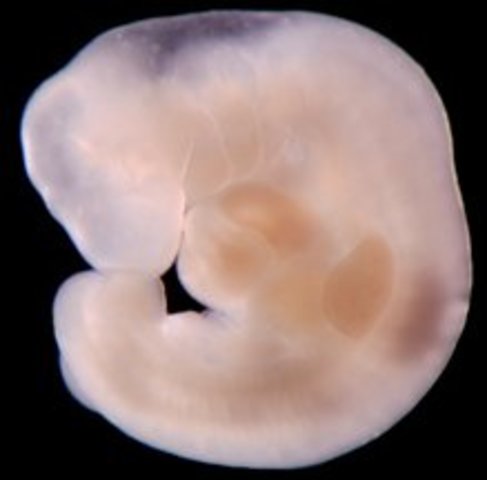

• week 6

week 6

Embryo is about 8 mm in length. Spinal cord begining to close.

• week 8

week 8

Baby starts to move. Face is beginging to take shape.